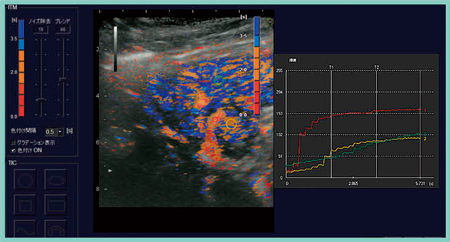

この画像に対して,各画素の時間的な輝度変化を色付け表示するInflow Time Mapping(ITM)解析を行ったところ,動脈の後に,門脈と同じようなタイミングで腫瘍が濃染され,その後,肝実質が染まる様子が観察された。Time Intensity curveでも同様の造影効果が確認された(図6)。

図6 ITM解析